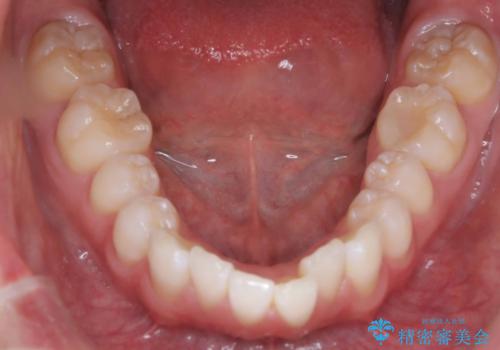

- 「歯のでこぼこを治したい 1年くらいで矯正を終わらせたい」を主訴に来院された患者様です。

叢生量は多く無く歯の傾斜も標準傾斜だったので歯は抜かずにワイヤー矯正で治療を行いました。